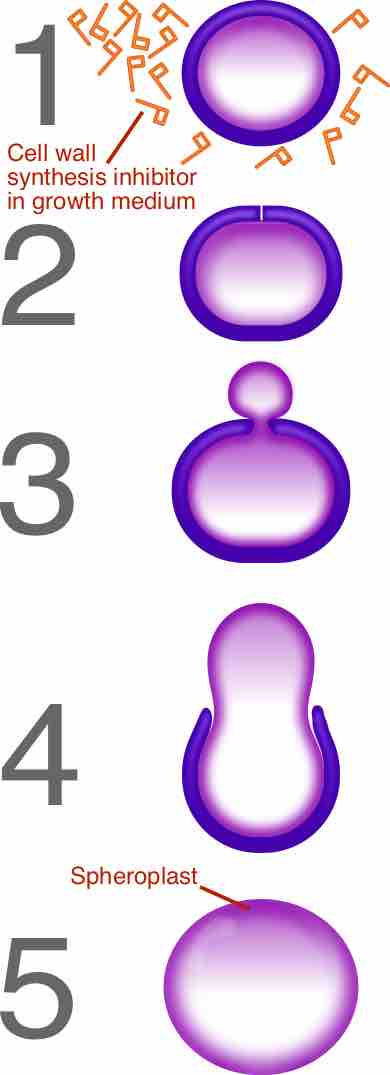

β-Lactam (beta-lactam) and glycopeptide antibiotics work by inhibiting or interfering with cell wall synthesis of the target bacteria.